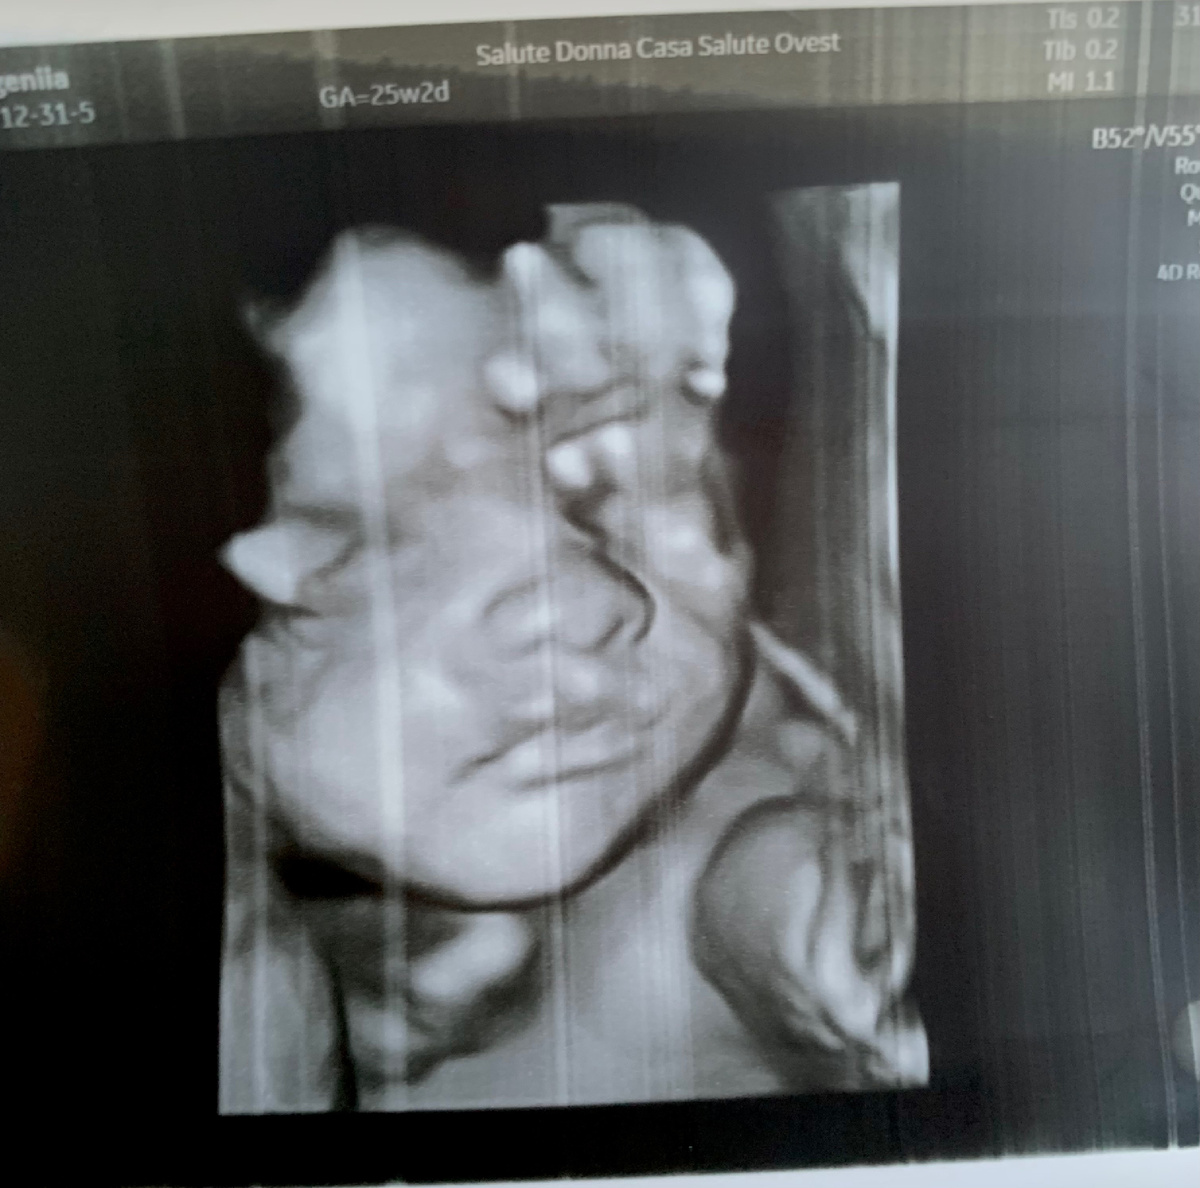

Осмотры и узи мне проводили раз в месяц, иногда чаще. Повторюсь, что все исследования и даже назначенные витамины были для меня бесплатными.